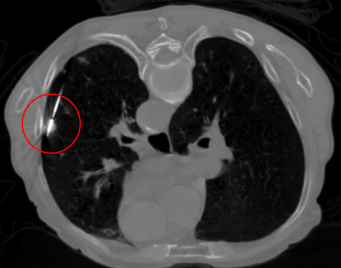

考慮到患者情況,我院呼吸與危重癥醫學科王開金副主任組織肺結節與肺癌MDT討論,征得患者及家屬同意后,決定為患者實施微波消融術。1月9日由王開金副主任帶領的呼吸介入團隊,在CT引導下為患者行局麻下肺結節微波消融術。手術順利,術中患者無不適,術后恢復良好。

微波消融術中